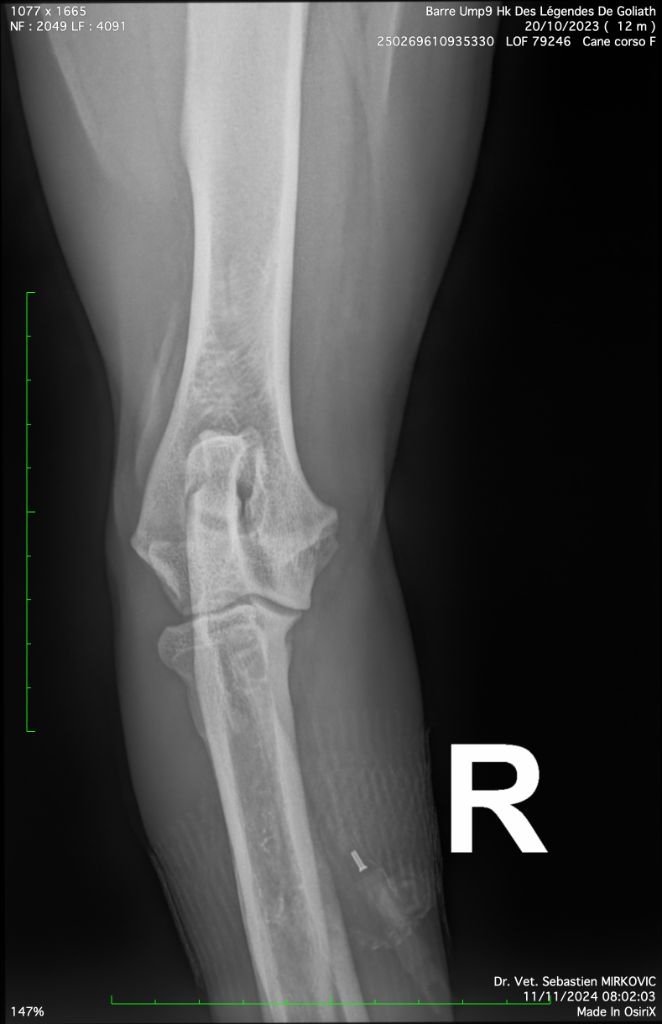

Ump9 hk des Légendes de Goliath

Cane Corso

20/10/2023

| Couleur | NOIRE. DRSA N/N HD B / ED 0 |

| Puce | 250269610935330 |